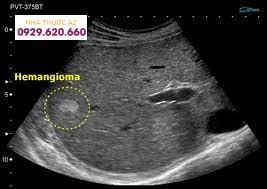

Hình ảnh u gan trên kết quả siêu âm

U máu gan biểu hiện thường là một phát hiện tình cờ trong quá trình siêu âm bụng và được mô tả là tổn thương đơn độc hoặc nhiều tổn thương. Chúng có thể giới hạn ở một thùy (nhiều hơn ở thùy gan phải) hoặc mở rộng ra toàn bộ gan. Theo kích thước của chúng, chúng có thể nhỏ hoặc khổng lồ (> 5 cm) và có thể dài từ 1 mm đến 50 cm . U máu gan được phân loại theo bản chất của chúng là u máu thể hang, mao mạch và xơ cứng; loại sau được đặc trưng bởi sự thoái hóa và thay thế sợi và có thể bị chẩn đoán nhầm là khối u ác tính